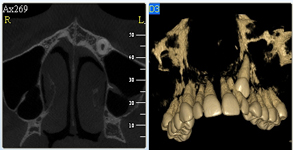

Je speciální zubní digitální tříprostorový tomograf (3D), který umožňuje na základě jediného snímkování vytvořit všechny typy RTG zobrazení, které jsou pro lékaře potřebné. Díky používané technologii tzv. „kuželového paprsku“ a speciálním senzorům je výrazně zmenšená dávka záření - o více jak 80% proti klasickému CT vyšetření. To je významné zejména u dětí. Pomocí tohoto přístroje je možné zjisti skutečnou situaci v čelistních kostech pacienta tedy množství kosti - můžeme změřit skutečnou šířku i výšku kosti, i kvalitu kosti (hustotu) v místě uvažované implantace. 3D (tříprostorové) zobrazení umožňuje zvýšit prostorovou představu operatéra ještě před vlastní operací a zároveň pacientovi lépe objasnit a ukázat oblast plánovaného zavedení implantátu.

Pacient „neumí číst“ RTG snímky, ale díky 3D zobrazení vidí „svoji skutečnou čelist“ - např. jak je nízká či úzká, vidí průběh nervu nebo velikost čelistní dutiny, což mu umožní i pochopení nutnosti v některých případech provést pomocné zákroky ještě před vlastním zavedením implantátu (viz. kostní štěp, sinus lift, kostní granulát...).

Vyšetření pomocí tohoto přístroje používáme i ve stomatochirurgii (zlomeniny čelistí, zuby moudrosti, cysty, onemocnění čelistního kloubu), ortodoncii (retinované zuby, nadpočetné zuby), parodontologii atd.